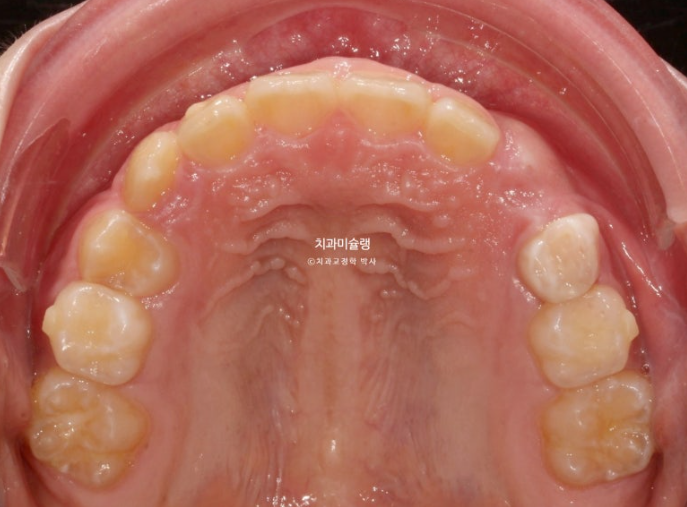

2년 전 교정치료를 위해 온 만 10세 어린이 입니다.

앞니가 하나 들려있고 깊게 물리는 과개교합이 있습니다.

중심선 불일치도 보입니다.

윗니 돌출이 측면에서 잘 보이네요.

영구치날 공간은 비교적 양호한 편입니다.